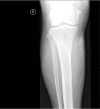

We present a case of calcifying panniculitis due to calciphylaxis in a nontherapy compliance 65-year-old man suffering from chronic renal failure. Calciphylaxis, a life threatening condition, is characterized by high calcium x phosphate product, presence of calcium crystals in the skin and secondary hyperparathyroidism. The clinical presentation includes painful firm plaques, which could progress to nonhealing ulcers. A review of literature is given with emphasis on identification of risk factors and early diagnosis.